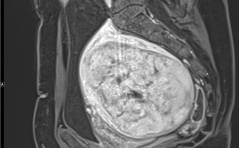

Im Bild – Harnverhalt durch grosses Hinterwandmyom – Ein der Sakkulation analoger Pathomechanismus

Eine 48-jährige perimenopausale Patientin beklagte einen immer wieder auftretenden Harnverhalt während der letzten Monate und stellte sich deswegen in unserem Beckenbodenzentrum vor. Abhilfe verschaffte lediglich ein Lagewechsel und die sportliche ... PDF Dokument